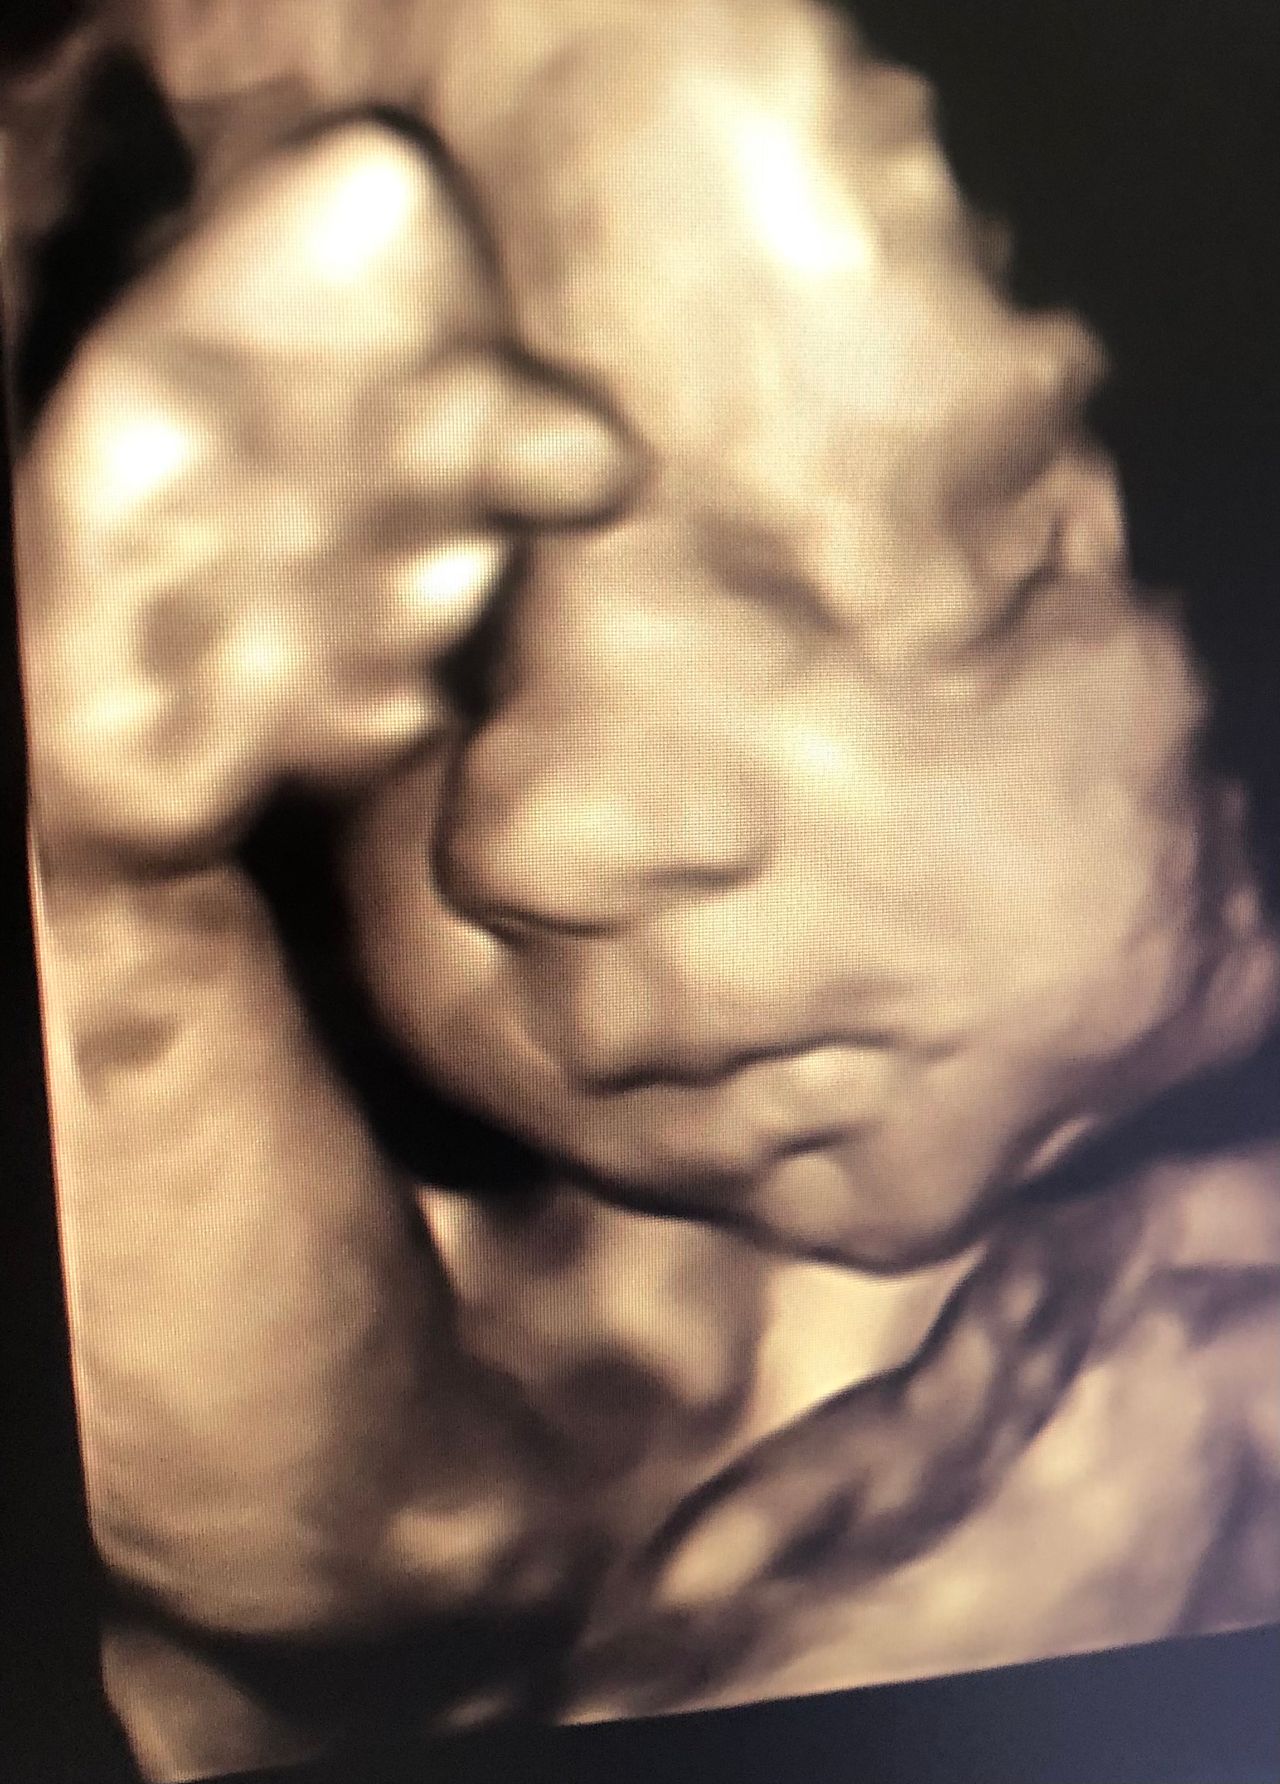

Zdjęcia i filmy

Moje zainteresowania zawodowe obejmują diagnostykę ultrasonograficzną, nieinwazyjną i inwazyjną płodu, terapię płodu, wszelkie problemy ciąży wysokiego ryzyka i zagadnienia w zakresie medycyny matczyno-płodowej, patologii porodu i połogu.